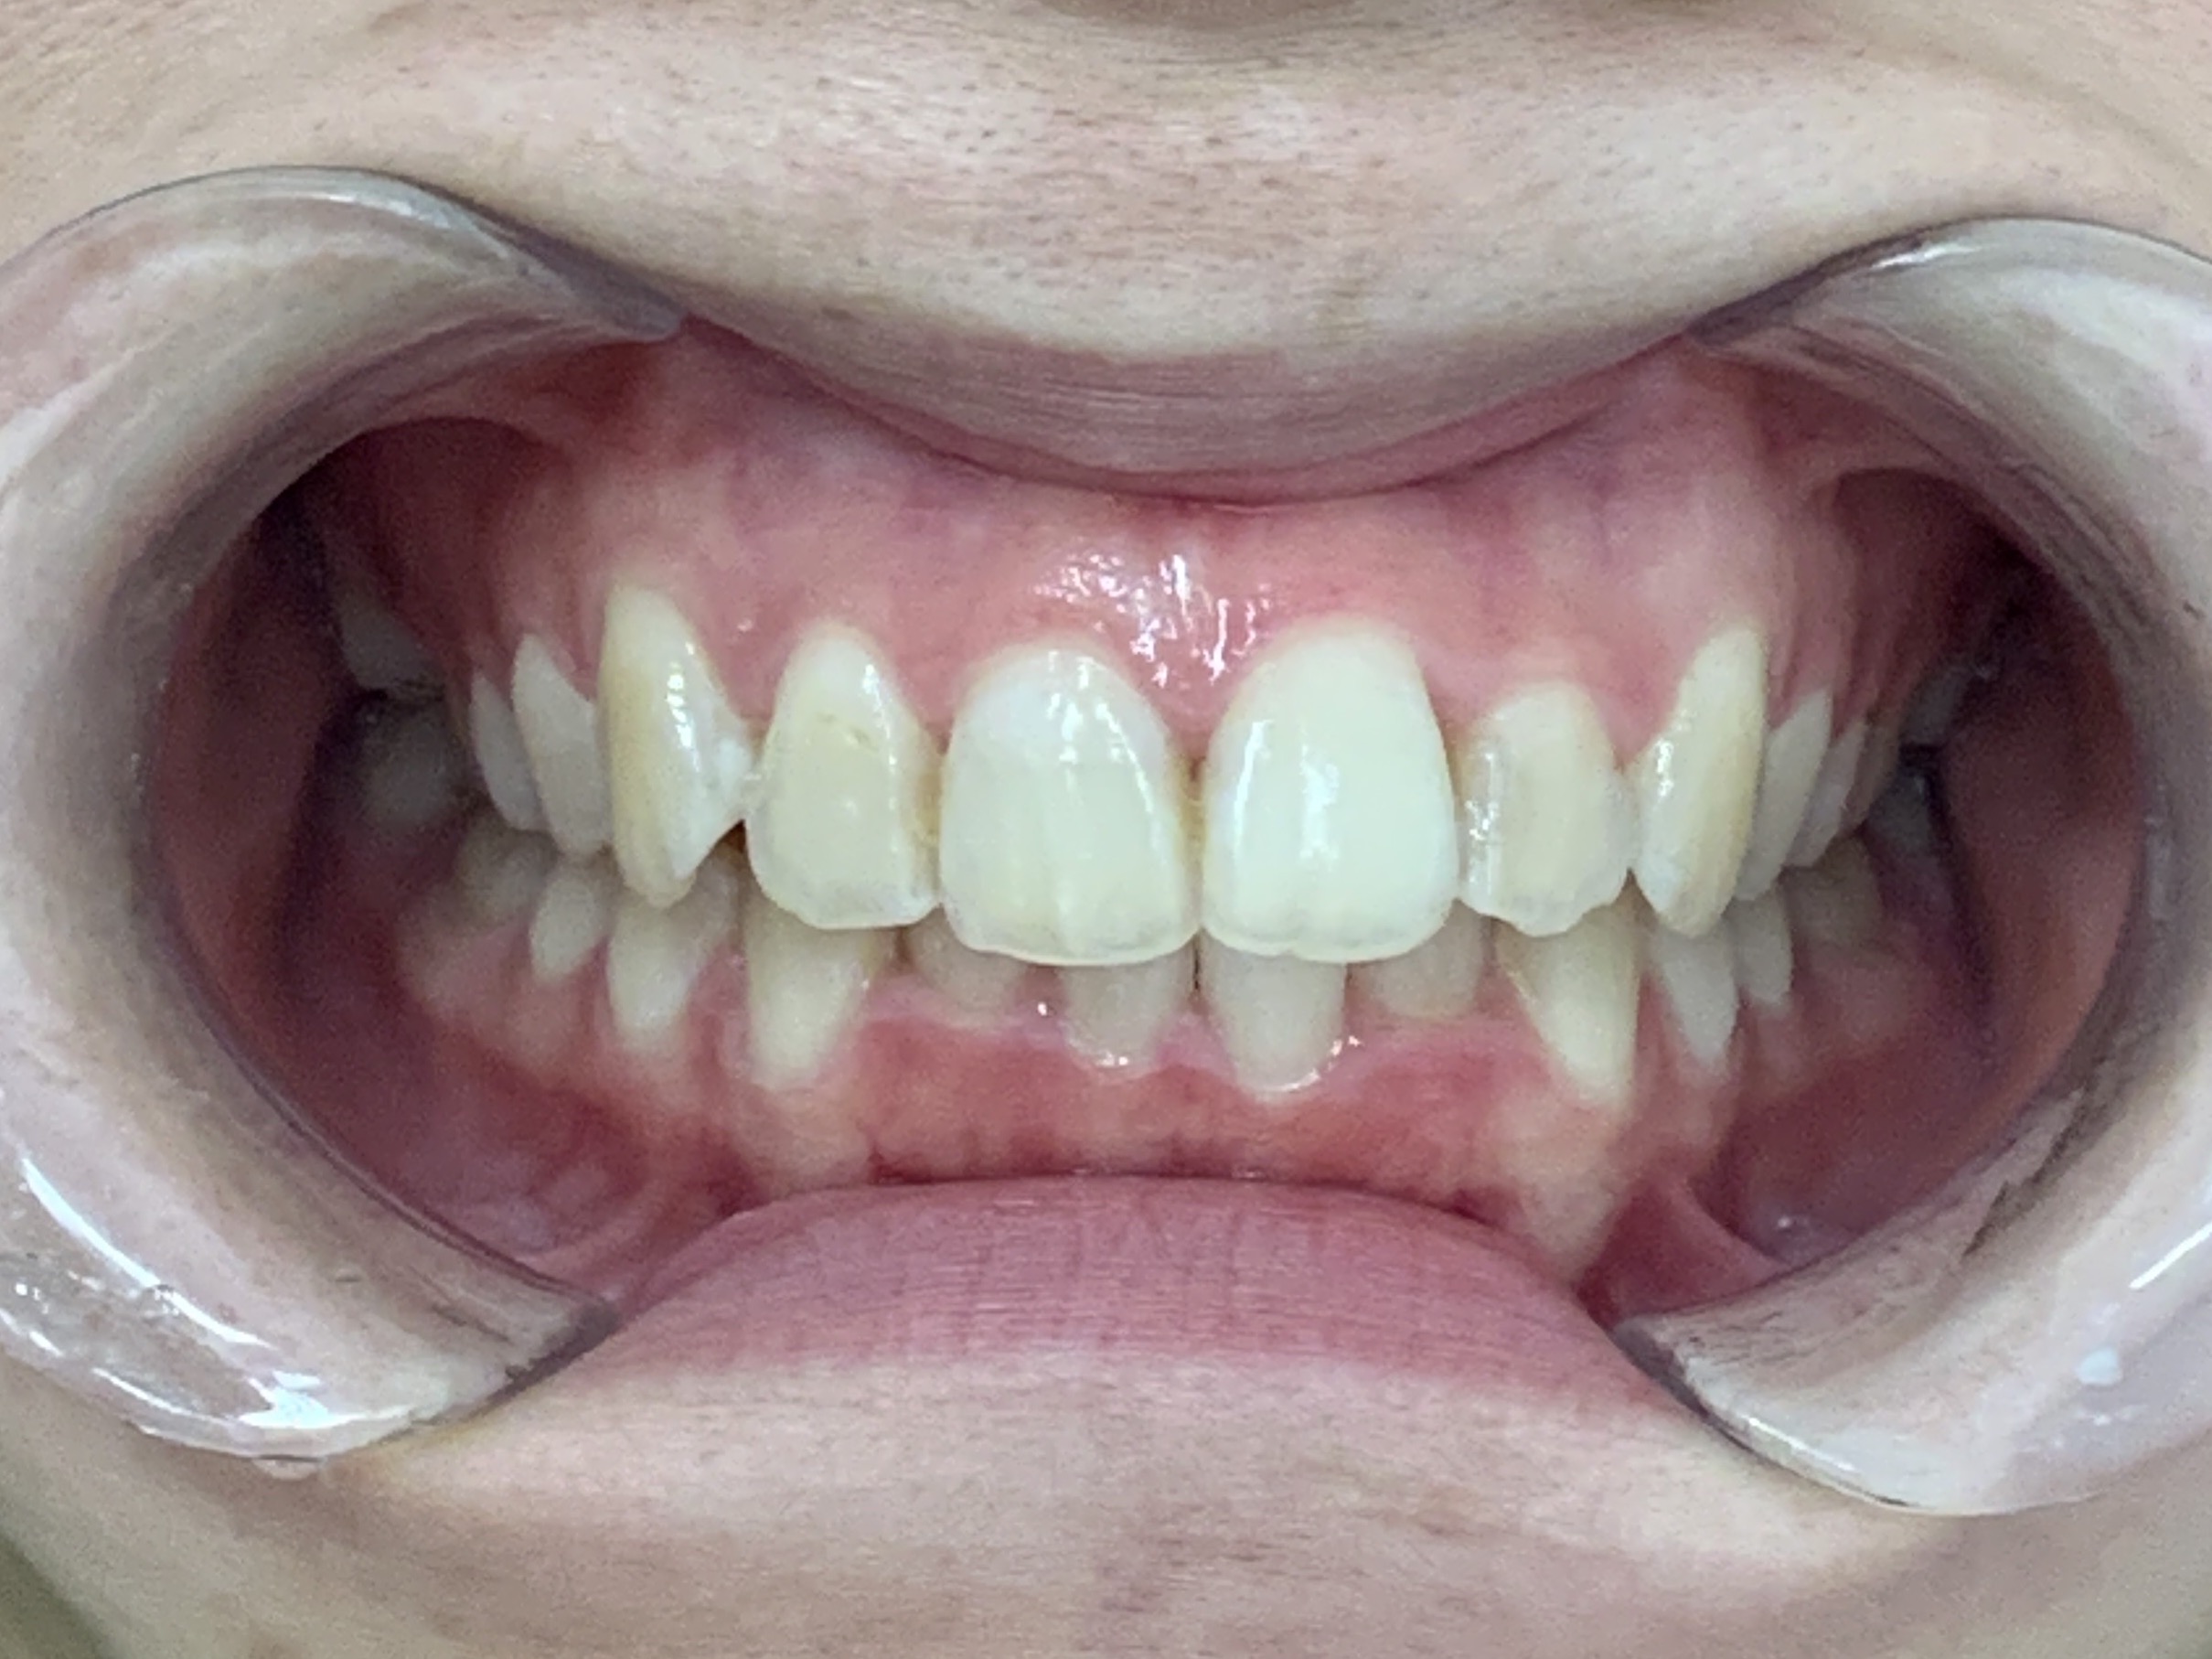

歯並びが改善し、見た目が良くなっただけでなく、前歯で物が噛みやすく歯磨きもしやすくなりました。

下顎の叢生が少し残りましたが、上顎はきれいに並びました。

患者様からは「以前の歯並びよりきれいになって嬉しい」とご満足いただけました。